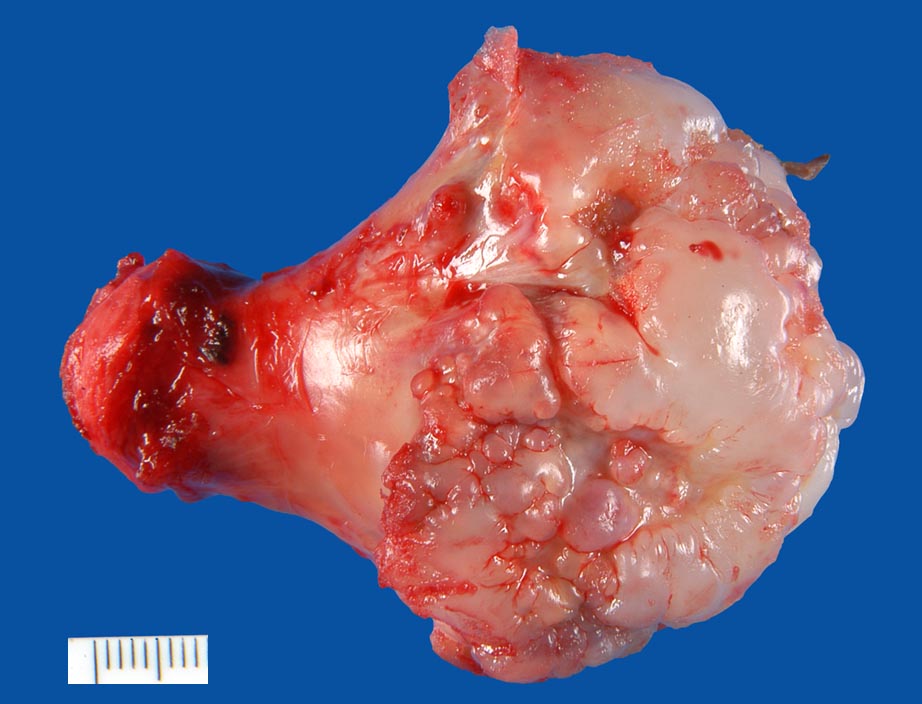

Der mediale Femurkondylus ist blumenkohlartig aufgetrieben und zeigt eine glasige gräuliche Oberfläche.

Auf lamellierenden Schnitten ein kortikaler Knorpelüberzug von max. 6,5mm Breite.

Gestieltes Osteochondrom distaler Femur rechts medial.